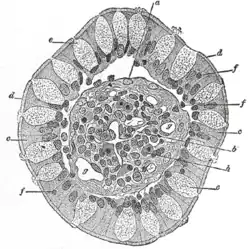

Glândula intestinal do intestino humano

Glândula intestinal do intestino humano -